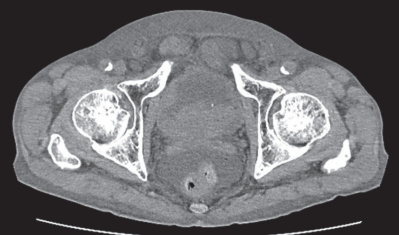

尿所見:蛋白(-)、糖(-)、ケトン体(-)、潜血 3 +、沈渣に赤血球 100 以上/HPF、白血球 1 ~ 4 /HPF を認める。血液所見:赤血球 285 万、Hb 8.5 g/dL、Ht 29 %、白血球 5,500、血小板 20 万。血液生化学所見:総蛋白 6.5 g/dL、アルブミン 2.8 g/dL、総ビリルビン 1.0 mg/dL、AST 26 U/L、ALT 15 U/L、LD 136 U/L(基準 120~245)、尿素窒素 66 mg/dL、クレアチニン 5.1 mg/dL、尿酸 5.8 mg/dL、 血糖 93 mg/dL、Na 134 mEq/L、K 5.8 mEq/L、Cl 98 mEq/L。腹部超音波検査で両側の水腎症と尿管拡張、膀胱内に腫瘤を認めた。腹部単純 CTを別に示す。